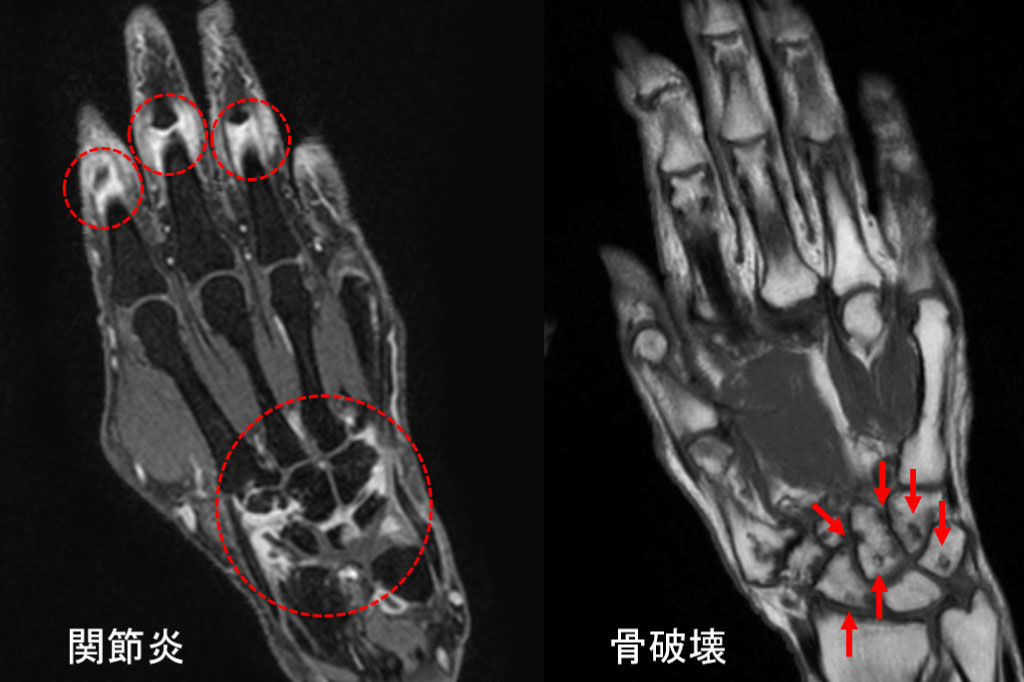

関節造影MRI検査

同一症例における関節造影MRIと関節エコーの比較(滑膜炎あり)

関節炎や骨の破壊を非常に鋭敏に検出します。両手・両手指など複数の関節を同時に客観的に評価することが可能です(上の写真)。

また、骨髄浮腫を捉えることで、将来的な関節破壊のリスクを予測することもできます。関節炎の評価においては、関節造影MRIは関節エコーと比較して、より高感度に病変を検出することが可能です(下の写真)。

当クリニックでは早期関節リウマチの診断に際して、画像診断専門クリニックと連携し、積極的に関節造影MRIを用いることにより、関節炎の検出感度を最大限に上げるよう工夫しております。

これまでに関節造影MRIを1500件以上施行した実績があります。